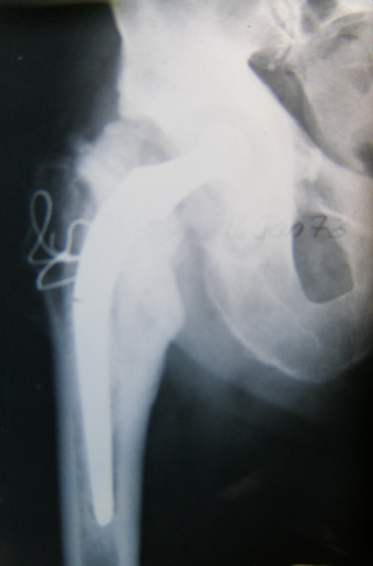

Case study broken prosthesis stem